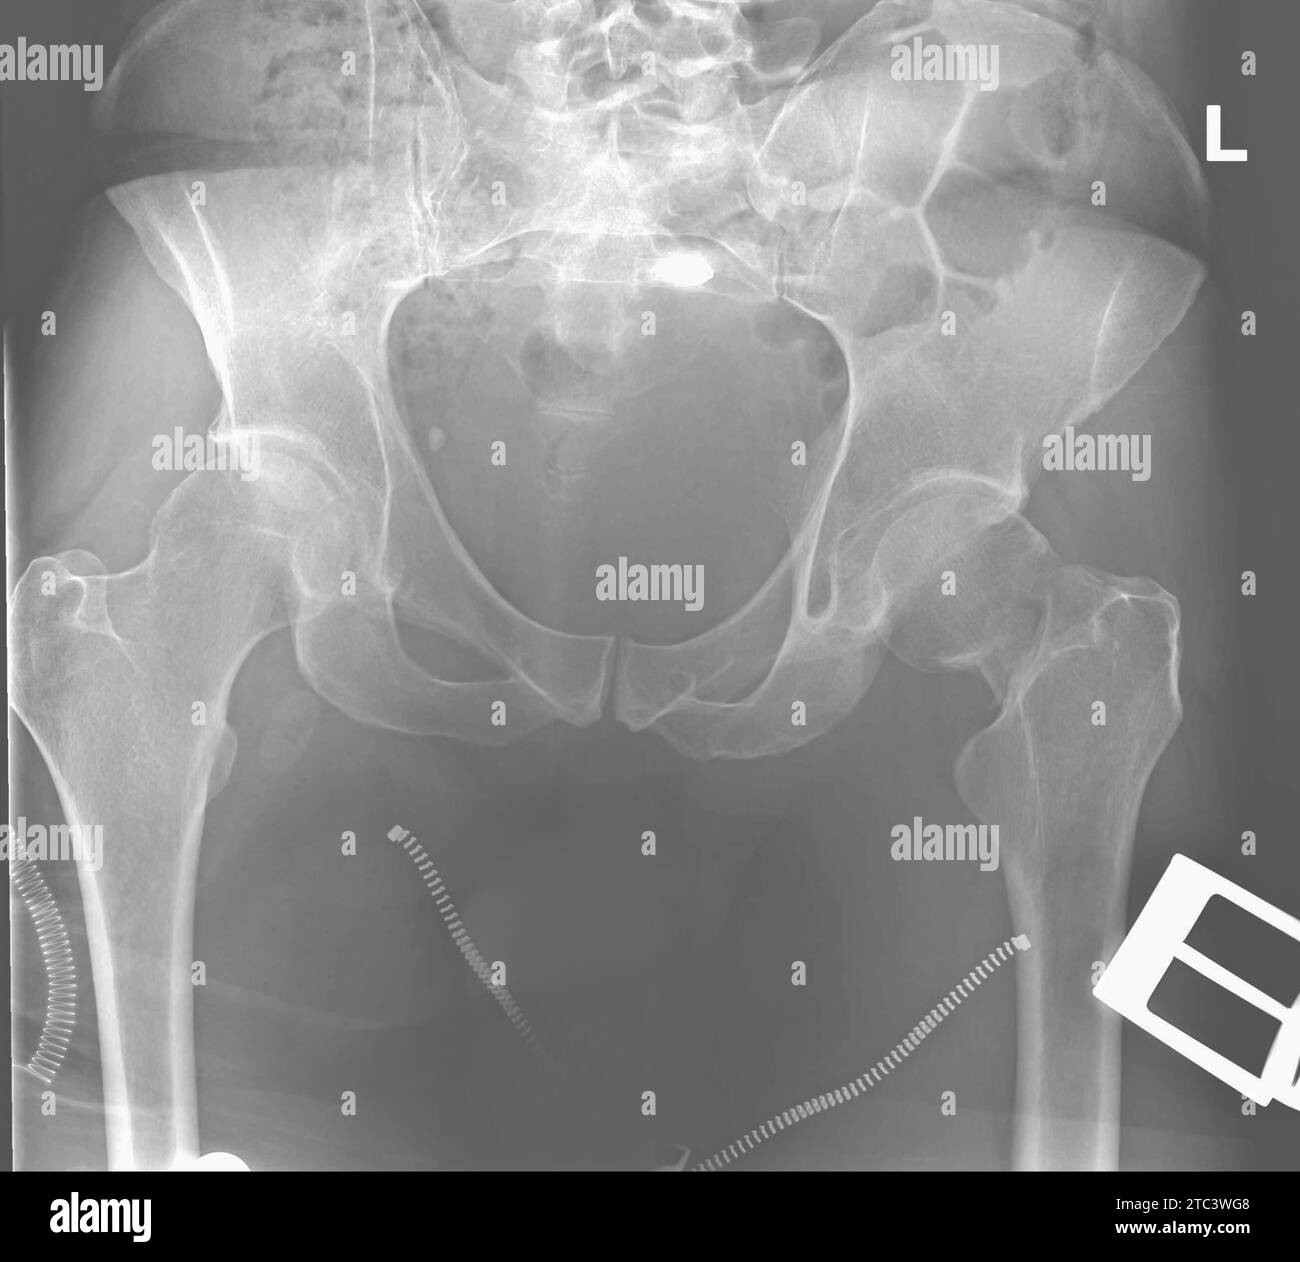

Left femoral neck fracture. Xray photo of man. Roentgenogram. Next day Fracture X Ray Chest Should this patient undergo imaging to determine if he has a rib fracture? rib fractures are frequently associated with chest injury and are associated with significant pain and other. Trachea, carina, bronchi and hilar structures. the chest is normal on auscultation. fractures of the sternum can result from both direct and indirect blunt force trauma to the. Fracture X Ray Chest.

From www.dreamstime.com